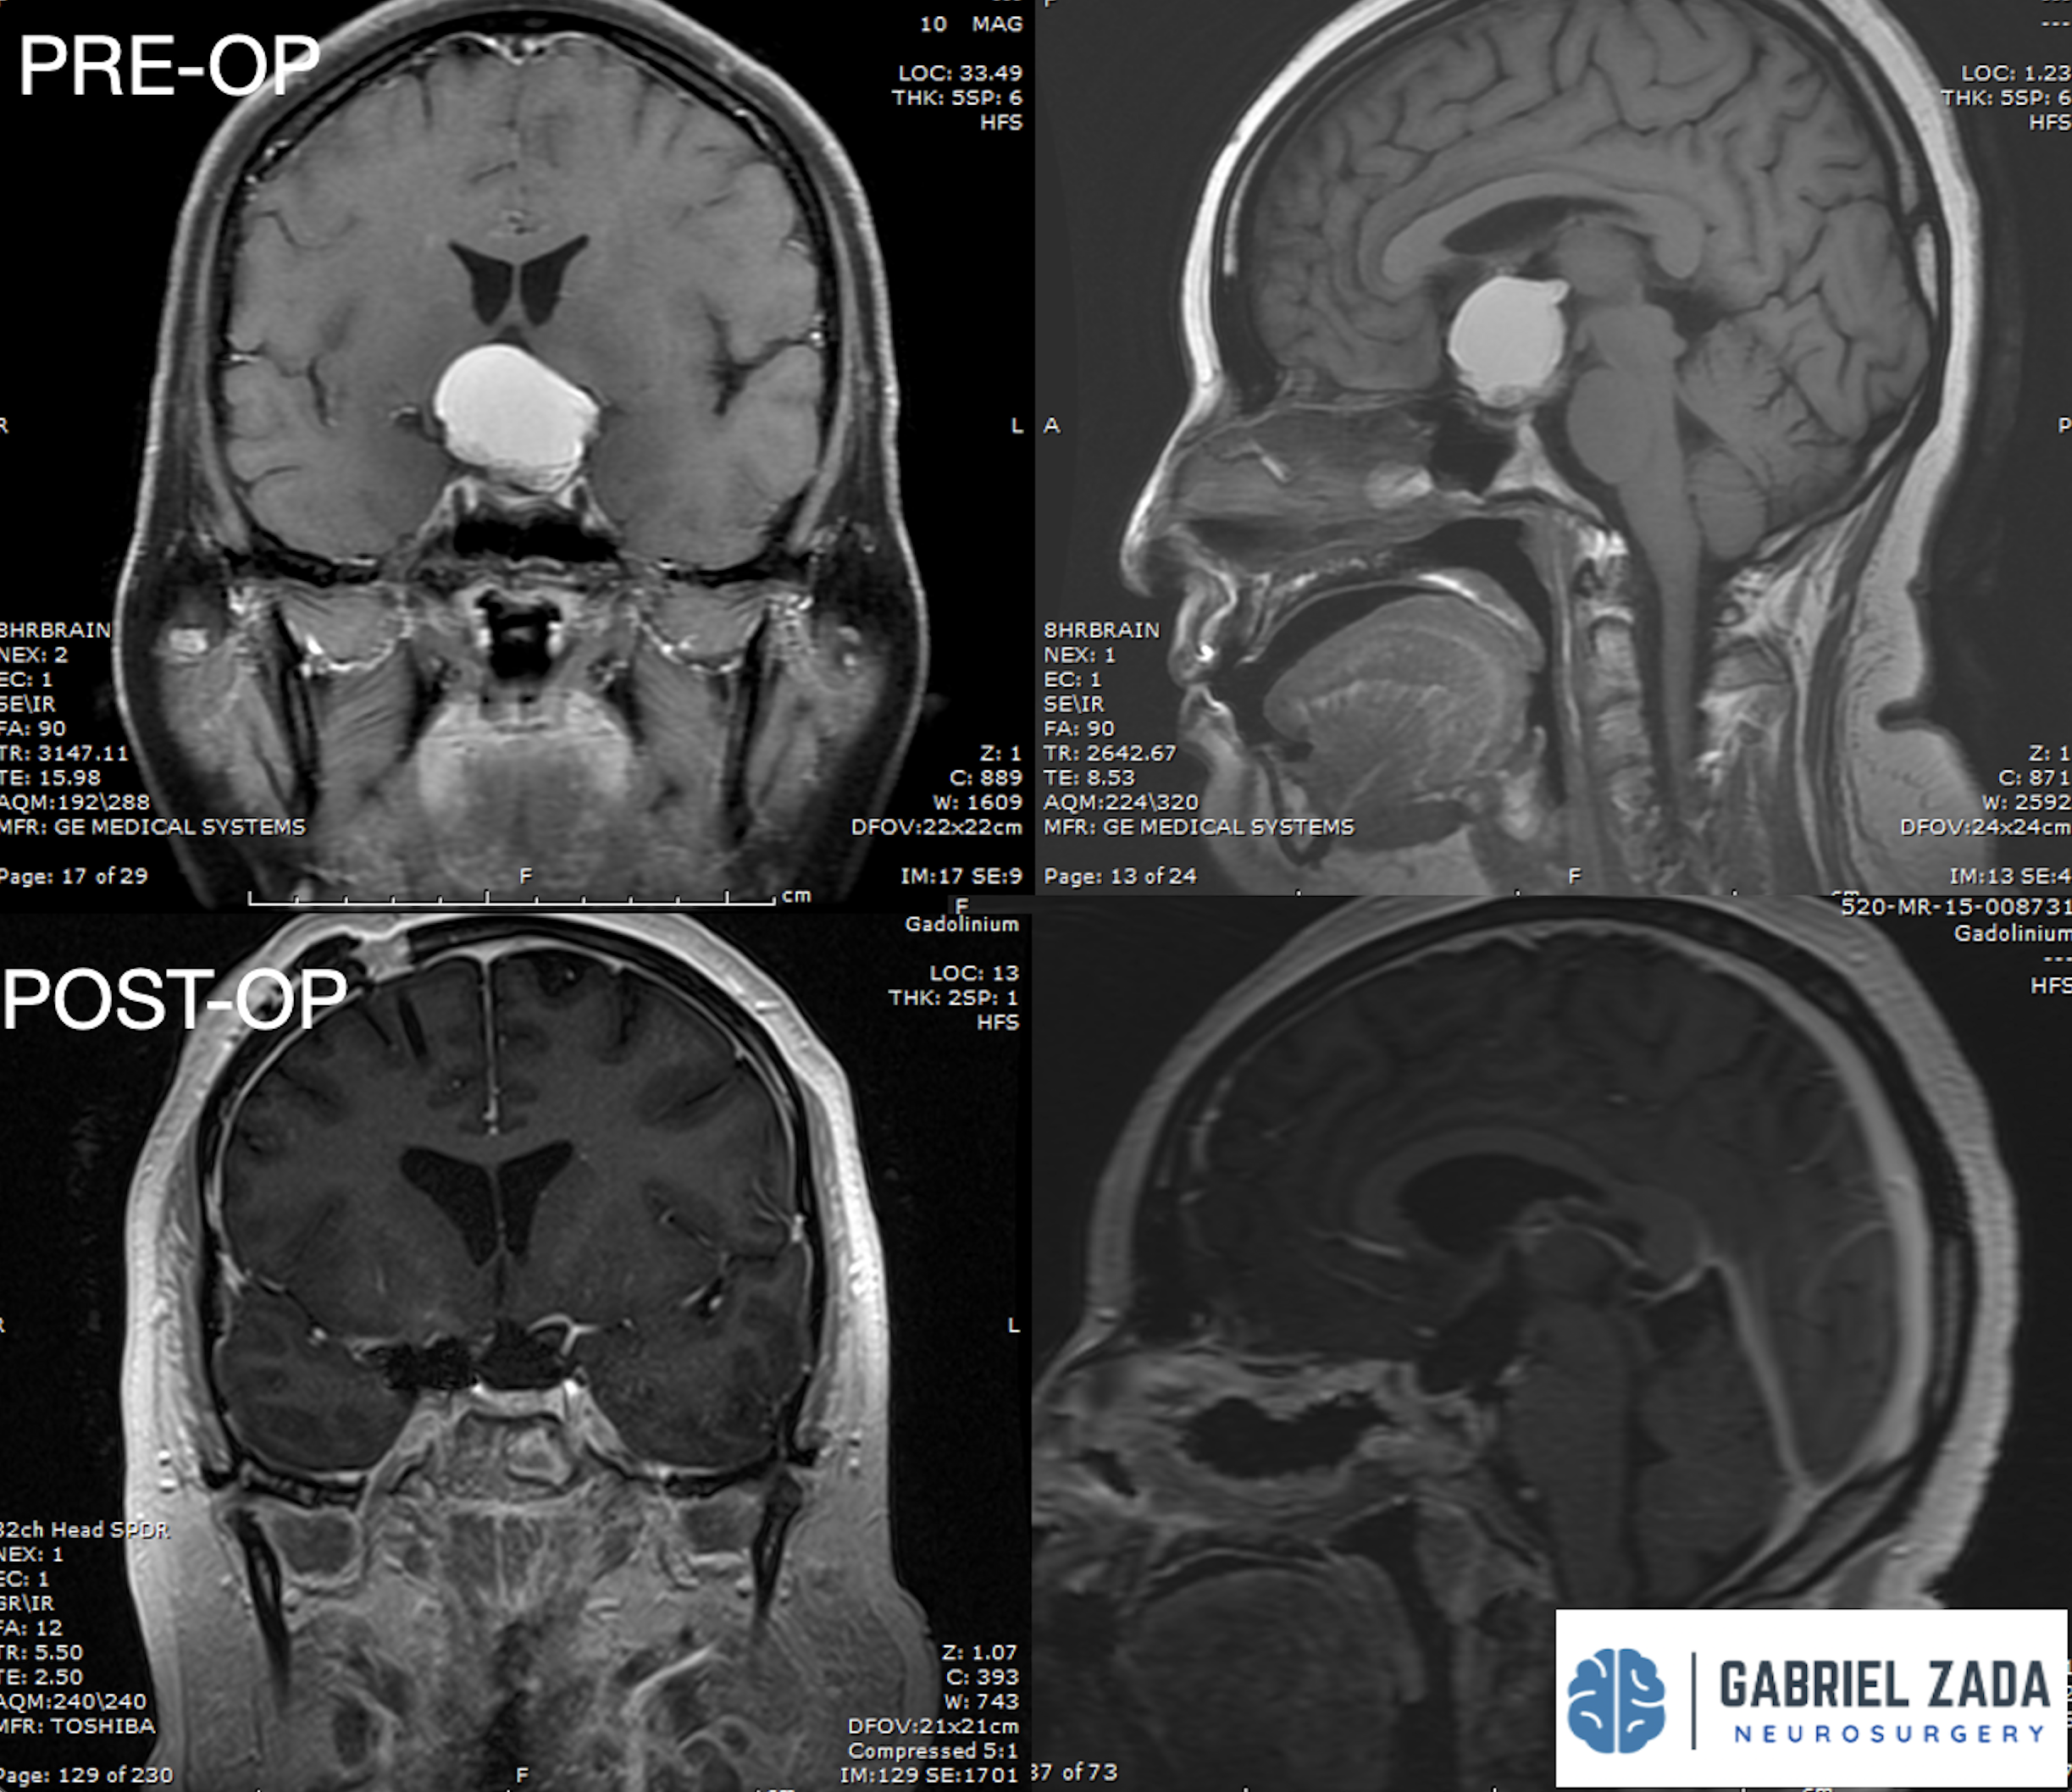

Explore this comprehensive gallery featuring pre‑ and post‑operative imaging of patients with skull‑base tumors treated by Gabriel Zada, MD, MS, FAANS, FACS. These cases highlight Dr. Zada’s expertise in advanced neurosurgical techniques and outcomes.

*Representative cases shown for educational purposes. All images de-identified. Individual results vary.